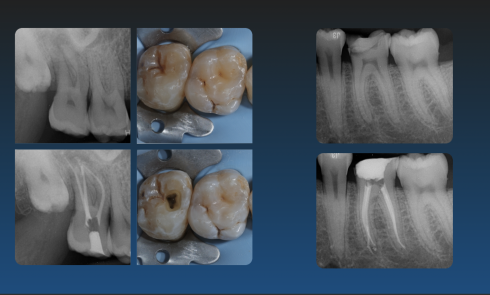

Je dispose de mon propre matériel et d'un portfolio de cas cliniques pour illustrer la qualité de mes interventions.